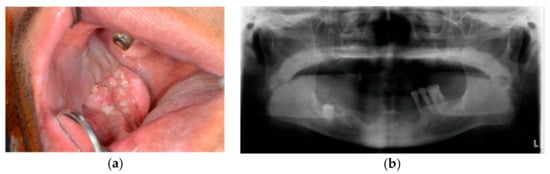

2.2. Surgical Technique